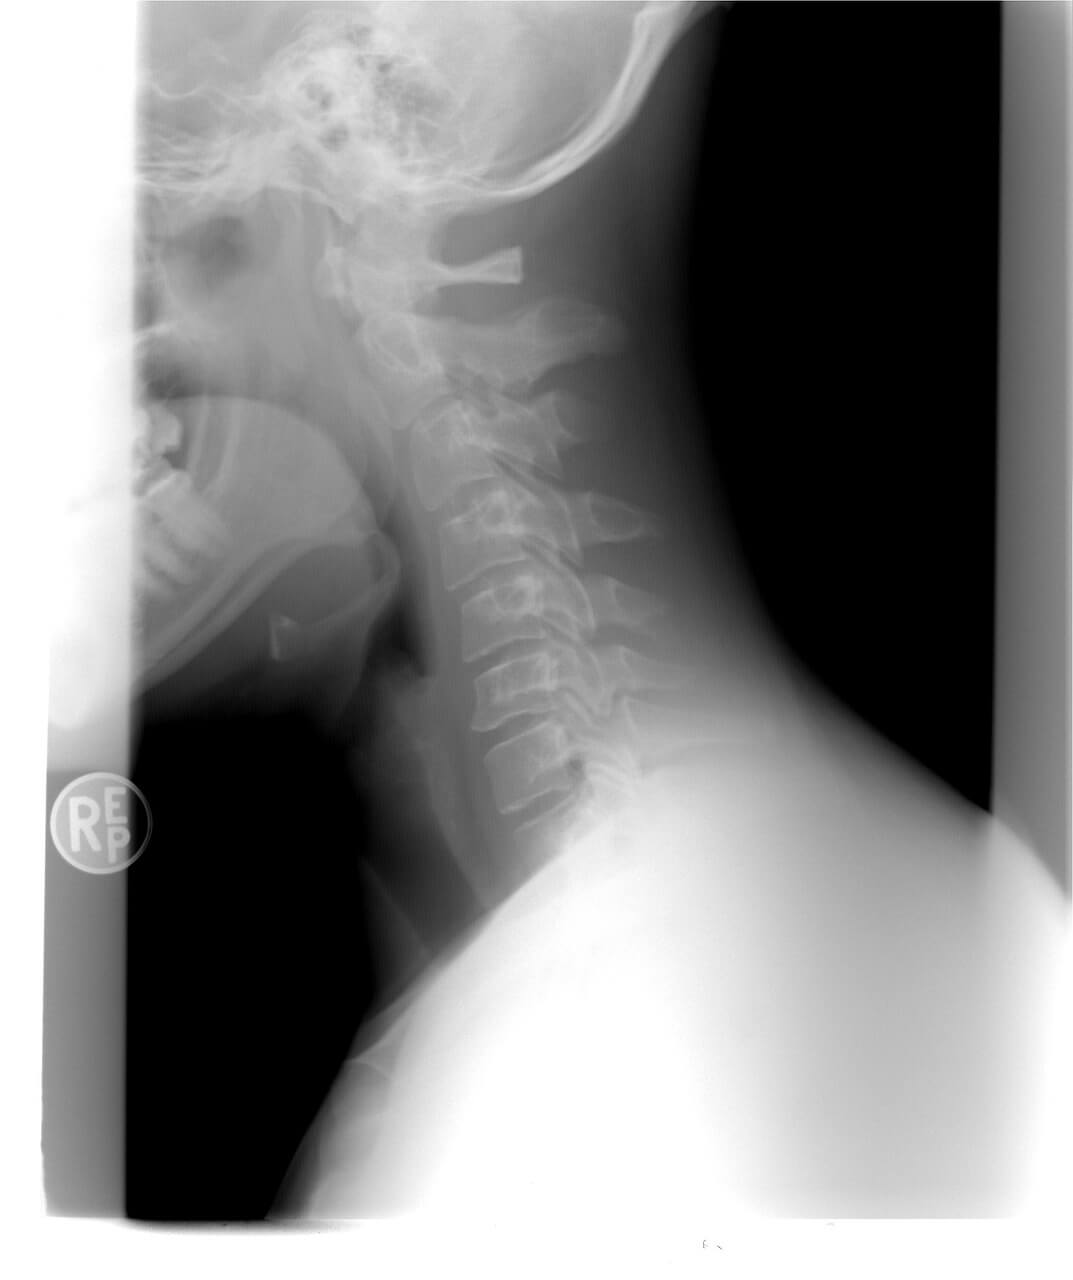

경추 디스크라고도 하며 목의 척추뼈 사이에서 충격 흡수 역할을 하는 쿠션과 같은 구조물입니다.

목 디스크는 유연성을 유지하고 목이 부드럽게 움직일 수 있도록 하는 데 필수적인 역할을 합니다.